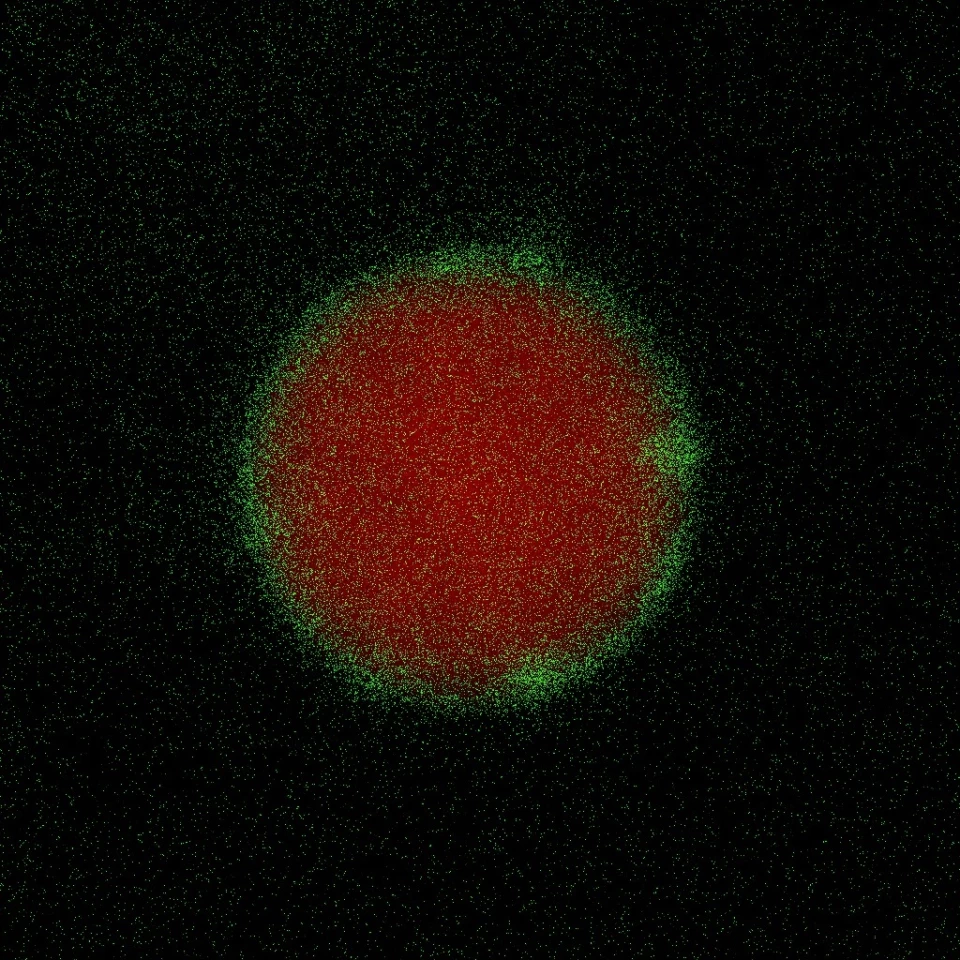

The nanoparticles developed by the team, containing a protein that rebuilds the blood-testis barrier